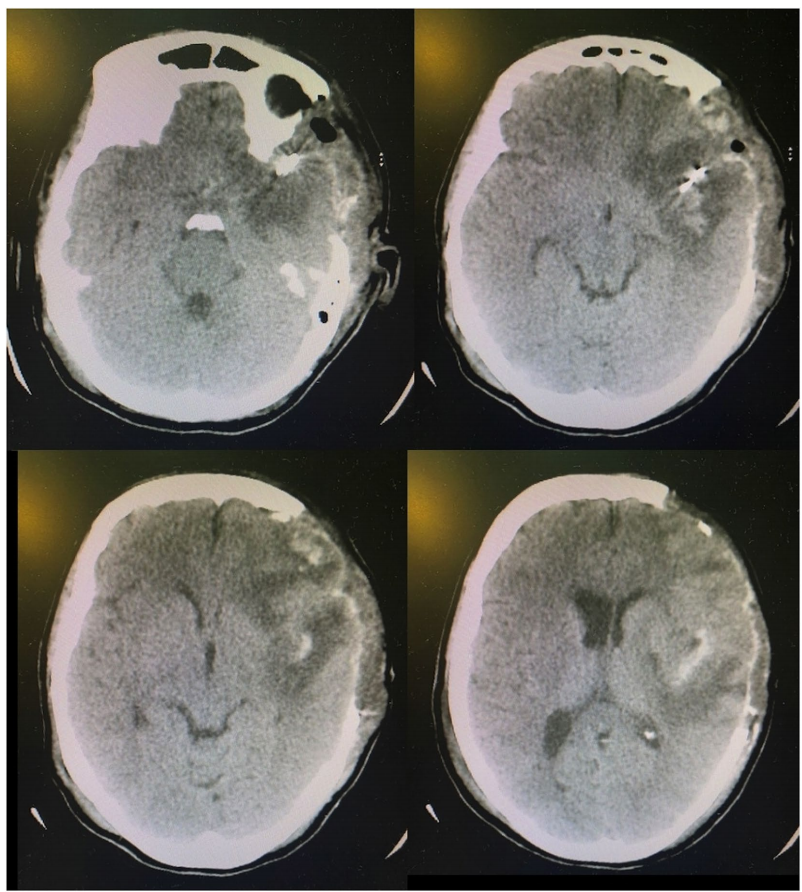

• • 一名17岁的男性患者遭受了一次机动车辆导致的头部伤害。他最初的GCS评分为8,院前无低血压或低氧情况。初步的头部CT扫描如图1a,b所示。没有明显的肉眼可见的损伤或肿块,分类为Marshall II。通过硬脑膜下颅压监测显示为对渗透治疗、中度过度通气和吲哚美辛止痛药无法控制的颅内高压情况。第二次头部CT示硬膜下积液,无占位效应(图1c,d)。使用巴比妥类药物后患者颅内高压仍未控制,遂进行了腰大池置管引流,颅内压得到了控制(图1)。患者最后预后良好,GOSE评分为8。

图1 案例1。a,b初始CT扫描,无肉眼可见的脑损伤。c,d第二次CT显示硬膜下低密度影,无占位效应。图表显示平均每小时的平均ICP。治疗干预措施如框内所示(渗透治疗、巴比妥类药物和腰大池外引流术)